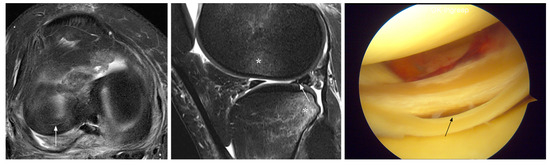

3.1. Unavoidable Errors

| 5 | M, 18 | 41 | normal | upper surface tear posterior horn | acute | R |

| 6 | M, 18 | 25 | normal | tear posterior horn | acute | PM |